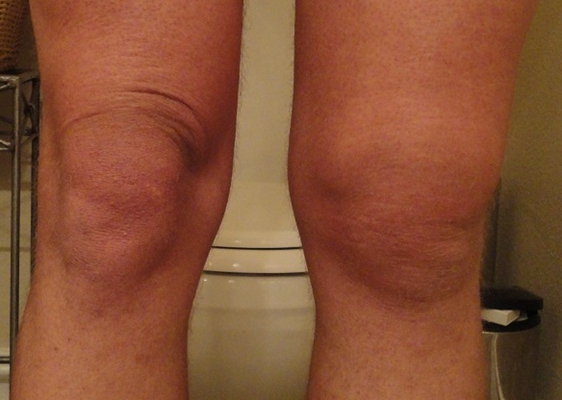

骨癌圖片

骨癌